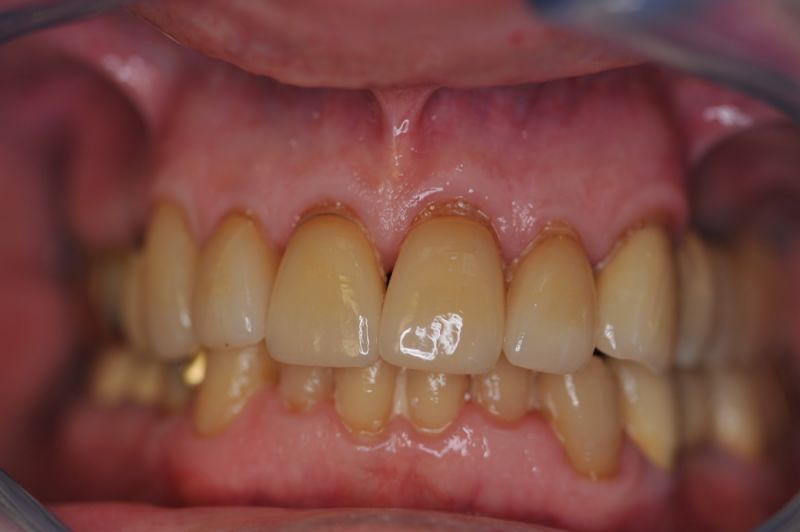

Die funktionstherapeutische Rekonstruktion befindet sich seit 17 Jahren im Munde des Patienten.

Gemeinsam ist man der Auffassung, dass sich heute zum Glück auszahlt, dass man beizeiten die Fundamente im Mund geschaffen hat, von denen der Patient heute im Alter zehrt.